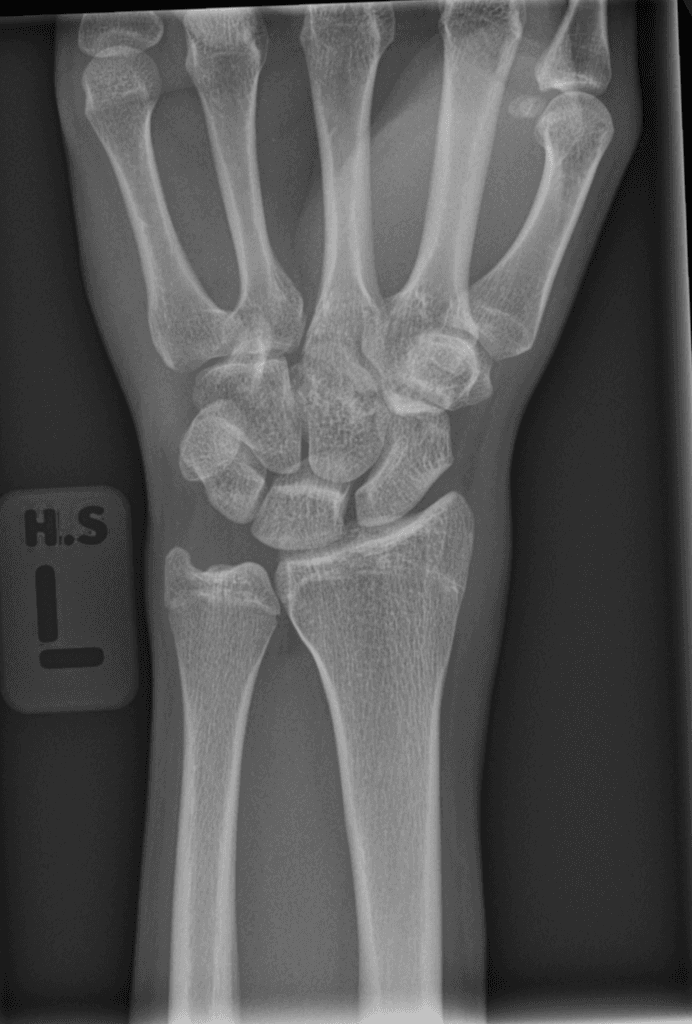

Frontal

X-ray•Frontal•1 Img

Ngã chống bàn tay ở tư thế duỗi

Ghi nhận trật khớp vai phải ra trước và xuống dưới. Không thấy hình ảnh gãy xương. Phần mềm bình thường.

Trật khớp vai ra trước

Ngã chống bàn tay ở tư thế duỗi (FOOSH) thường dẫn đến việc truyền lực qua các xương cổ tay đến xương quay và xương trụ. Các tổn thương thường gặp bao gồm gãy đầu dưới xương quay, gãy xương thuyền và gãy chỏm xương quay tùy thuộc vào độ tuổi và tư thế của cánh tay khi va chạm.